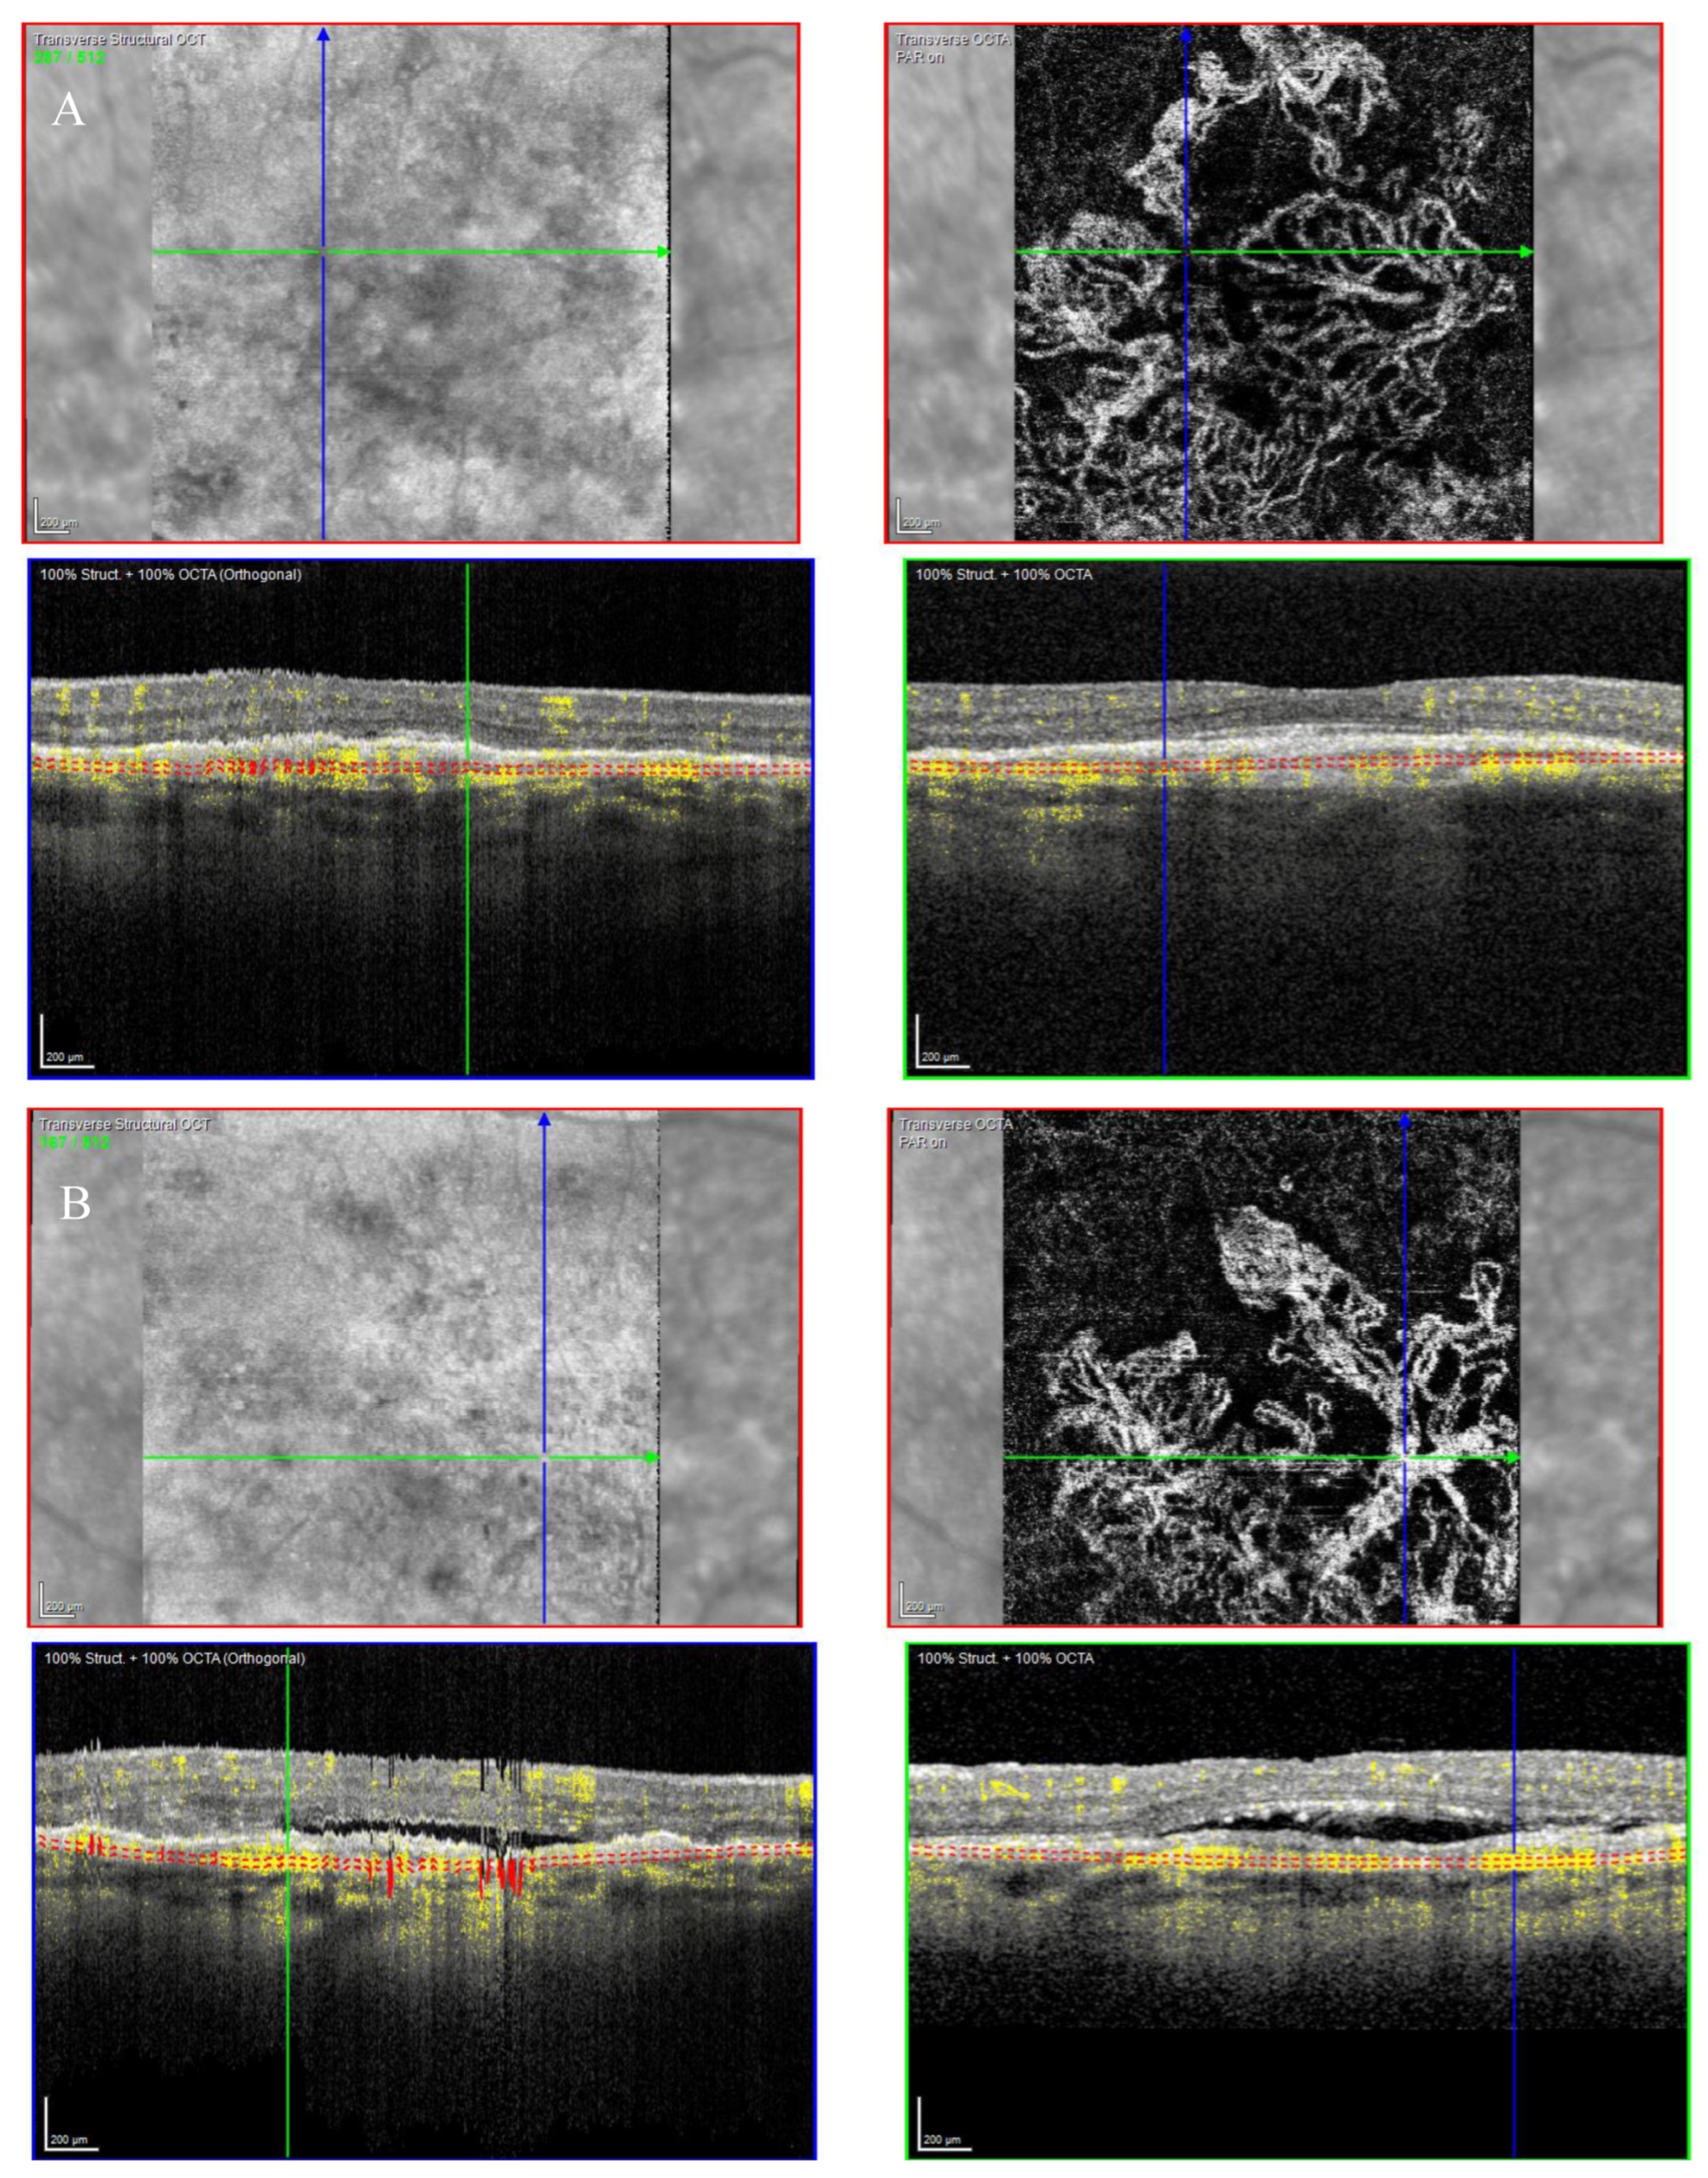

Fundus examination showed macular drusen in the right eye and a macular yellowish elevated lesion with retinal haemorrhage in the left eye (Figure 1A). Autofluorescence imaging (FAF) showed a hypoautofluorescent macular lesion in the left eye (Figure 1B). An OCT scan was performed, showing a dry macula with drusen in the right eye and a type 2 macular neovascularization (MNV) with subretinal fluid and splitting at the ellipsoid zone (EZ) creating a hypo-reflective cavity in the left eye; a hyper-reflective band, continuous with the EZ layer, was observed on the floor of the BALAD (Figure 1C).

Figure 1.

Case 1. Multimodal imaging features of bacillary layer detachment (BALAD) in a patient with left eye neovascular age-related macular degeneration. (A) Optos Ultra-widefield colour shows a macular yellowish elevated lesion with subretinal haemorrhage. (B) Optos Ultra-widefield autofluorescence imaging shows a hypoautofluorescent macular lesion. (C). Heidelberg Spectralis optical coherence tomography shows a type 2 macular neovascularization with splitting at the ellipsoid zone creating an hypo-reflective cavity and a hyper-reflective band on the floor of the BALAD. (D) Optical coherence tomography shows a complete resolution of BALAD after four anti-vascular endothelial growth factor intravitreal injections. (E) Heidelberg Spectralis optical coherence tomography shows a retinal pigment epithelial tear.

The optical coherence tomography angiography (OCTA) scan confirmed the presence of MNV in the left eye (Figure 2). Based on clinical findings and multimodal imaging, the patient was diagnosed with left nAMD. Anti-vascular endothelial growth factor (VEGF) intravitreal injections were commenced, according to a treat and extend (T&E) regimen. To date, the patient received four intravitreal injections. Since the first injection, the OCT scan showed a complete resolution of the BALAD (Figure 1D). However, a retinal pigment epithelium (RPE) tear was noted (Figure 1E). The BCVA did not improve (1.5 logMAR on the last examination).

Figure 2.

Case 1. Heidelberg Spectralis optical coherence tomography angiography shows a subretinal neovascular membrane in the left eye.

An OCT scan was performed showing a type 1 MNV with a haemorrhagic BALAD on the superior border of the nevus. The BALAD cavitation showed hyper-reflective material. Hyper-reflective granular foci at the ceiling of the BALAD were reported. The ELM was visible anterior to the BALAD (Figure 3C).

The OCT scan showed a right dry macula with drusen and a left macular type 1 MNV with a fibrovascular pigment epithelial detachment (PED), subretinal fluid, and a split at the myoid zone creating an intraretinal space with multiple hyper-reflective foci and a septa-like arrangement. A hyper-reflective granular band at the anterior border of the BALAD was reported. The posterior border showed a hyper-reflective thickened band. The ELM was intact, recognizable, and anterior to the BALAD (Figure 4D,E).

The OCT scan showed a type 1 MNV with subretinal and intraretinal fluid and BALAD in the right eye. The BALAD cavity presented hyper-reflective granular foci (Figure 5C).

The OCT scan demonstrated a type 1 MNV with PED and BALAD in the right eye. The ceiling of the BALAD presented hyper-reflective foci. The EZ zone was attenuated at the floor (Figure 12).

The term BALAD was recently introduced to indicate a splitting of the photoreceptor layer at the myoid level [1]. Assuming that the photoreceptors’ IS myoid is weaker than the ellipsoid and the junctional complexes of the ELM, it has been postulated that the main driving factor for developing BALAD could be the intrinsic weakness of the photoreceptors’ IS myoid [1,21,22]. When chorioretinal inflammation and exudation occur, the forces that promote the attachment of the photoreceptors’ outer segment (OS) to the RPE may be superior to the tensile strength of the photoreceptors’ IS myoid, resulting in splitting [1,21,22]. In nAMD, an IS photoreceptor shedding occurs due to degeneration. It may predispose nAMD patients to develop BALAD [23,24].

The non-haemorrhagic BALAD cavity showed hypo- or hyper-reflective material. In some cases, the hyper-reflective material may have a septa configuration. Some of our patients had a septa configuration of non-haemorrhagic BALAD. It is particularly evident in case reports 1 and 3.

We reported hyper-reflective granular foci at the ceiling of the BALAD. As reported in the literature, they could represent the myoid zone fragments and photoreceptors IS and OS. The ELM was visible superior to the BALAD on OCT scans.

We also observed a hyper-reflective band contiguous to an attenuated EZ on the floor of the BALAD. These findings have been reported in the literature [10,14,15,16,20,21]. Ramtohul et al. postulated that floor hyper-reflectivity could be related to the remaining mitochondria of the residual photoreceptor IS on the RPE–basal lamina–Bruch membrane complex. Alternatively, they hypothesized that the BALAD floor signal may be attenuated by the overlying fluid, the myoid fragments, and the OS attached to the RPE–basal lamina–Bruch membrane complex [21]. To date, a few studies have reported BALAD in neovascular AMD (nAMD). Thus, the incidence of BALAD in nAMD is not well defined. Sari Yordi et al. noticed that the bacillary detachment was present in 7.4% (6 of 81) of the eyes reviewed. It was predominantly associated with type 1 and 2 mixed MNV, higher fluid volumes, increased EZ attenuation, and sub-RPE disease [15]. Instead, Jae Hui Kim et al. reported an incidence of bacillary detachment in 4.5% (20 of 442) of the patients examined [16]. In a Korean cohort, Kim et al. observed that the incidence of BALAD was significantly different in the types of MNV. Type 2 MNV was found to be the most associated with BALAD [16]. These results accorded to the findings of Jung et al. [10]. Conversely, in the study by Ramtohul et al., type 1 MNV was reported to be the most associated with BALAD. They demonstrated BALAD in association with other MNV subtypes [20]. In our study, all cases presented a type 1 MNV, except for one patient who presented a type 2 MNV. Thus, our study is in agreement with the results reported by Ramtohul et al. The role of the presence of BALAD in the progression of nAMD is uncertain.